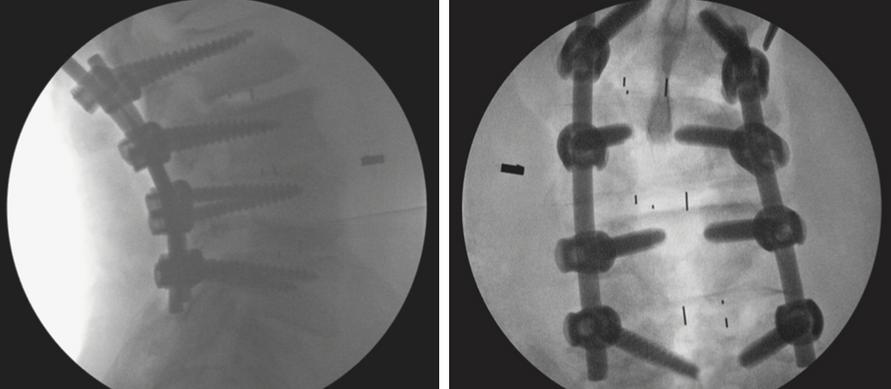

A B C

Figure 1: Illustrations of Cervical Decompression Procedure. Setting up the working tube and navigation: (A) The incision location was identified using a 3-dimensional navigation system (B) A 75-mm working tube was placed through the navigation probe,servingasabluntdilator (C)Thecorrectpositioningofthe workingtubewasconfirmedusingthenavigationsystem